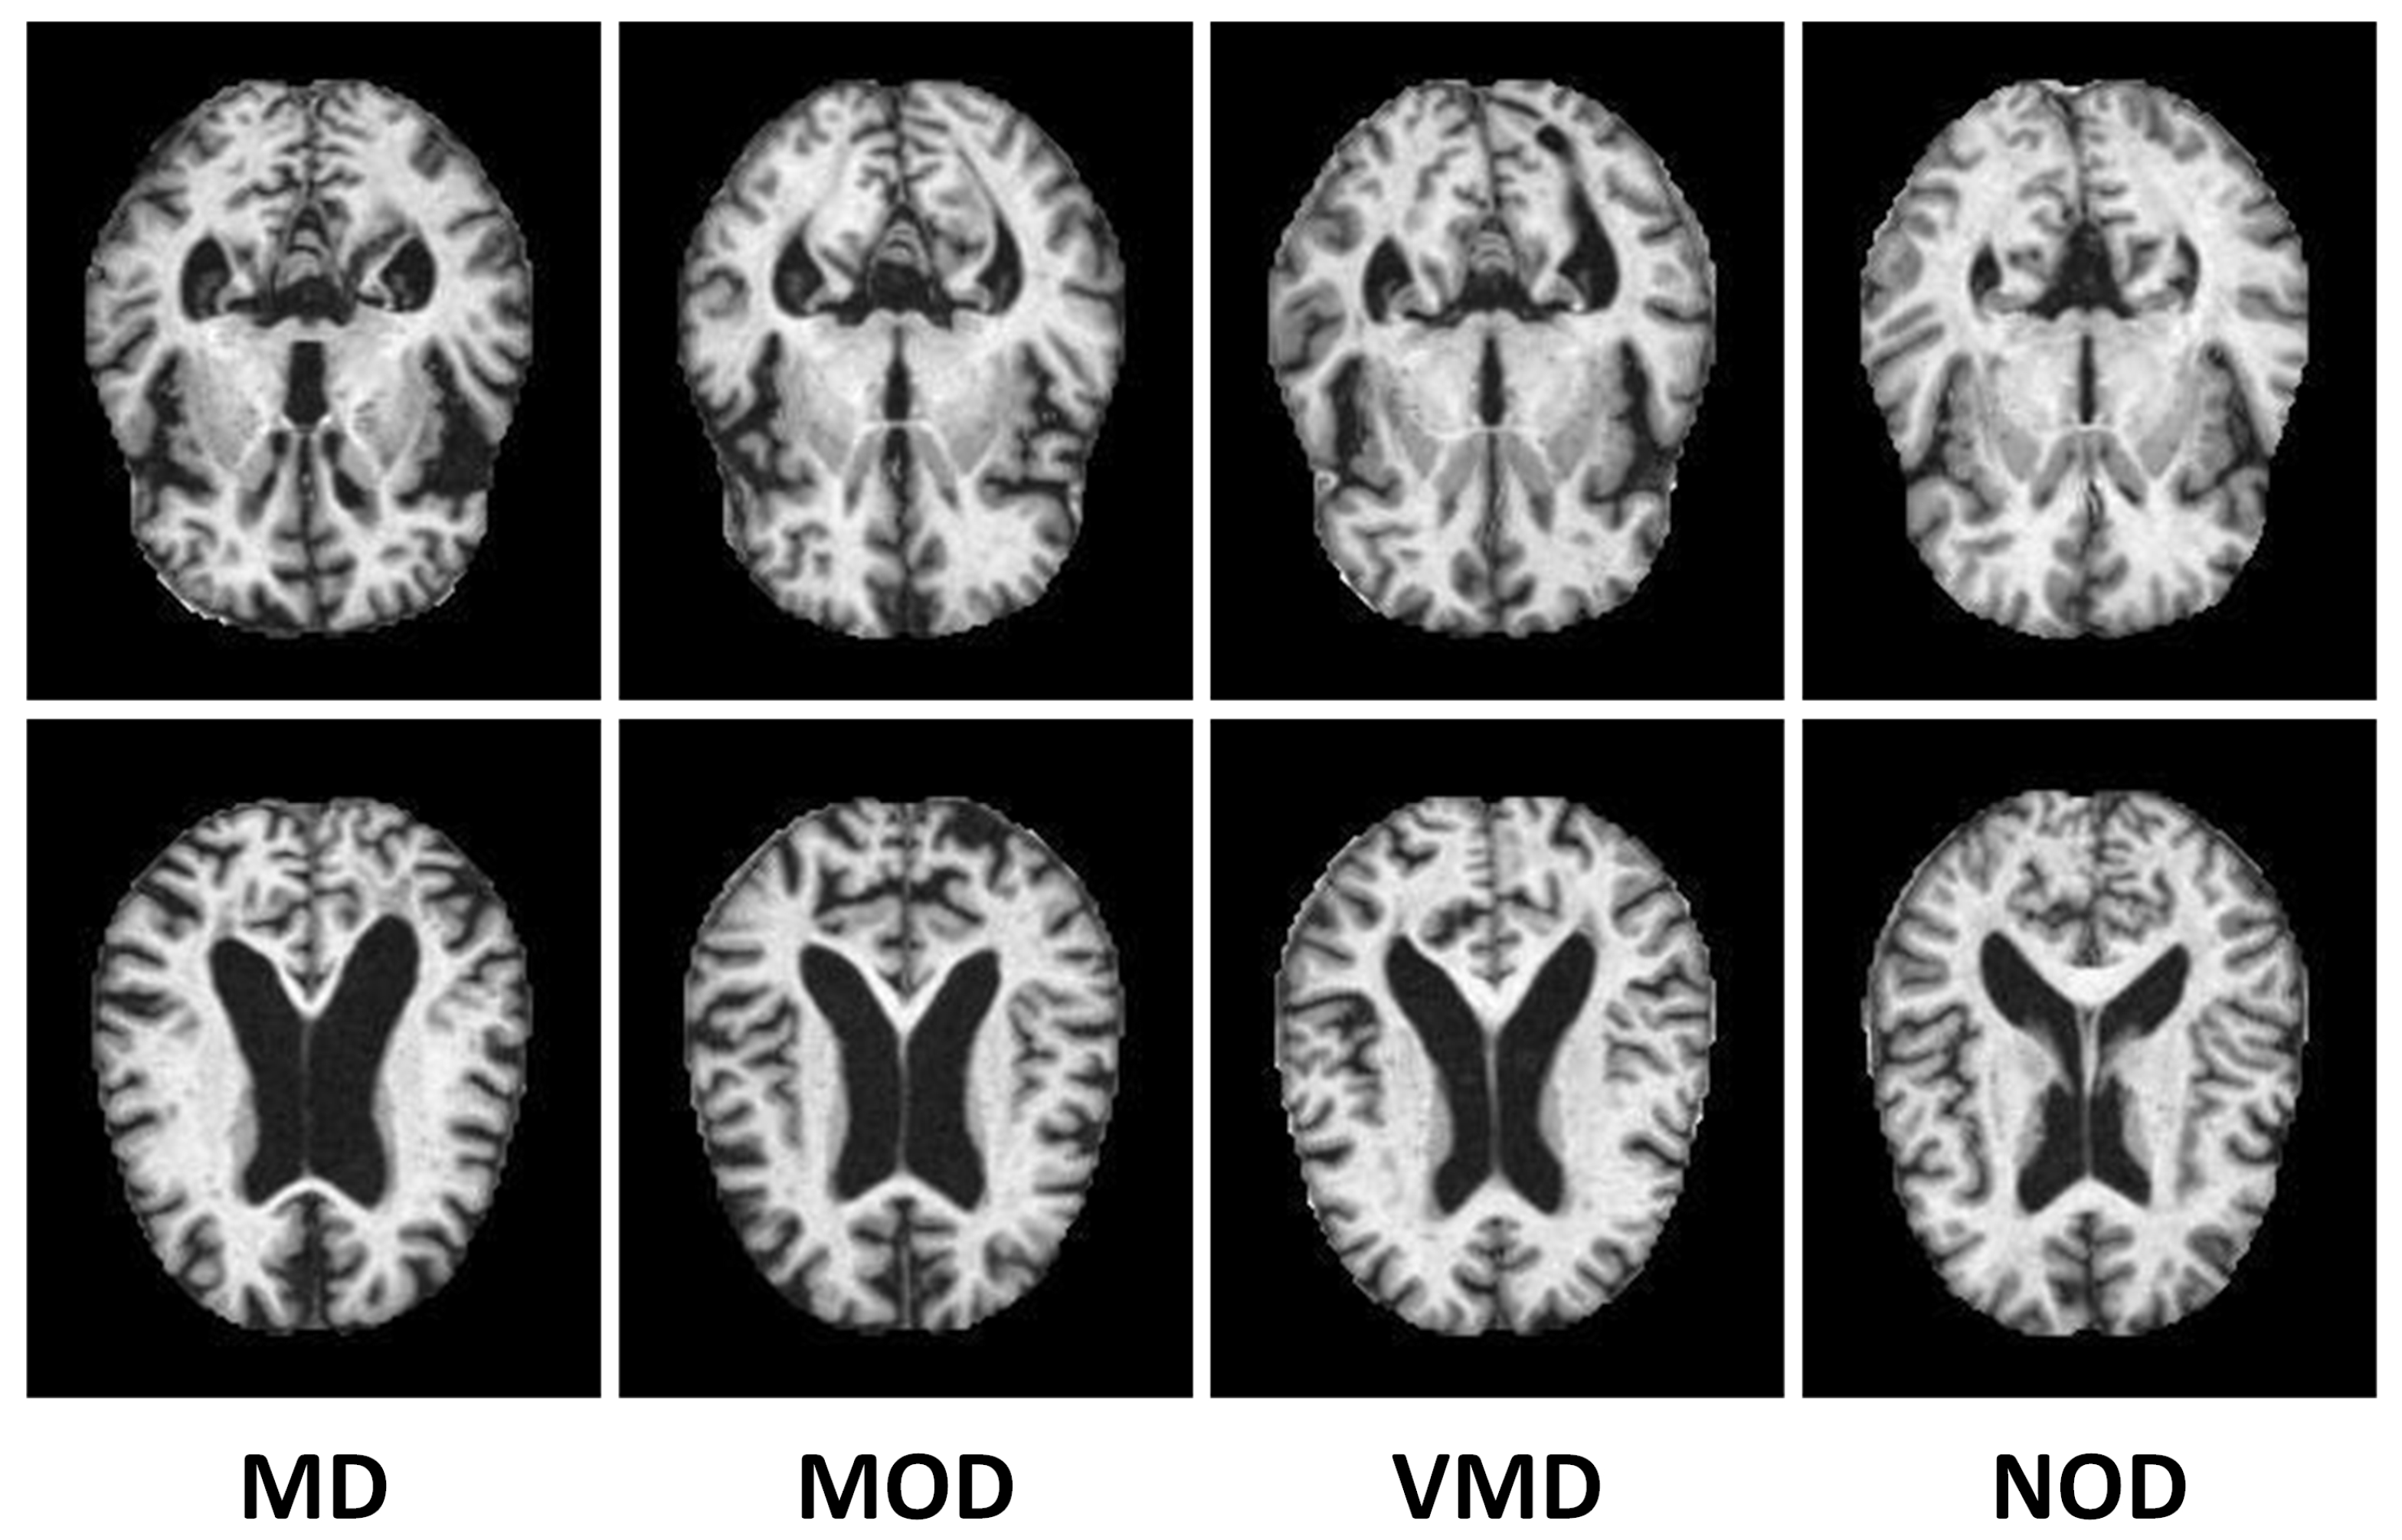

3.1. Description of the AD Dataset